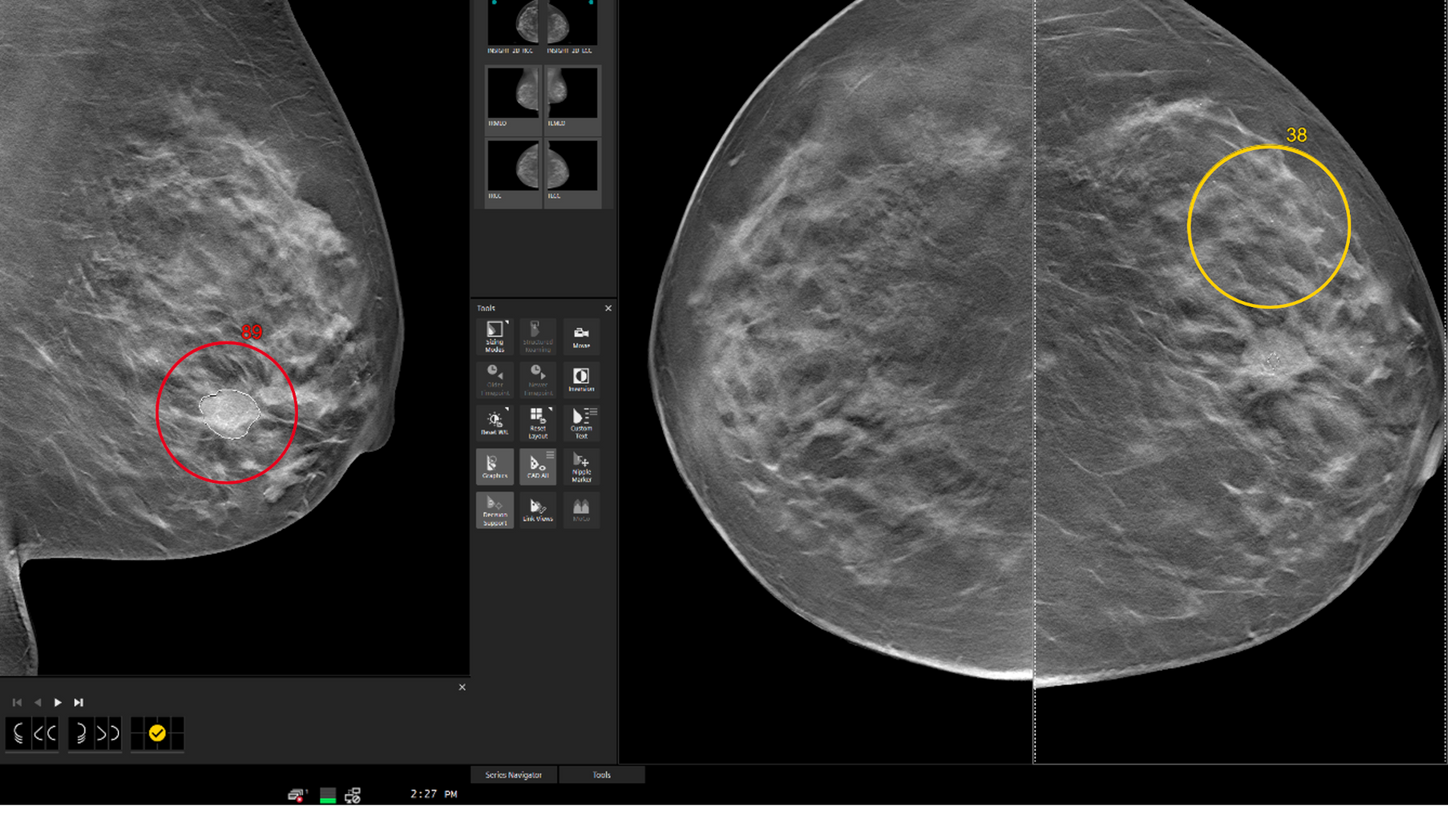

MAMMOVISTA B.smart deckt das gesamte Spektrum der Modalitäten ab – von der Mammographie über die MRT bis hin zum Ultraschall. Die agile, herstellerunabhängige Lösung bietet Radiolog*innen, die mit zeitaufwendigeren Tomosynthesebefundungen konfrontiert sind, eine hervorragende Performance.

- Entwickelt für eine hohe Geschwindigkeit

- Entwickelt für eine intuitive Nutzung

- Entwickelt für hervorragende Ergebnisse